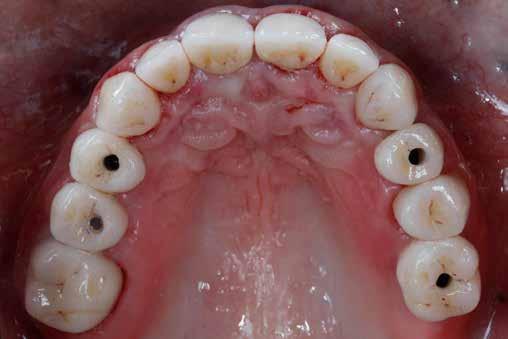

2. ábra: Az okkluzális nézet a fogszerkezet mennyiségét mutatja, a röntgenfelvételen az 1.5. fogon II. osztályú szuvasodás is látható. Még ha lehetséges is ezeket az eseteket koronahosszabbítással kezelni, a végeredmény átlagosan nem kielégítő. A ferrule gyógyulása korlátozott, és olyan parodontális szövődményekkel is találkozunk, mint a fekete háromszögek, a szomszédos fogak gyökérkitettsége. A fogszabályozó extrúzió sokkal előnyösebb.

A rendelésünkön egy 34 éves latin-amerikai nőbeteg azzal a panasszal jelentkezett, hogy a fogait „túl rövidnek” találja, és ezen felül a mosolyával sem volt megelégedve. Az anamnézisfelvétel alapján egészséges volt, elmondása szerint rendszeresen járt orvoshoz. Öt évvel korábban néhány hátsó fogát restaurálták. Páciensünk szájhigiénéje megfelelő volt,

a fogait rendszeresen ápolta. House klasszifikációja szerint, amely a pácienseket a fogászati kezelésekhez való attitűdjük szerint négy csoportba sorolja, a páciensünk a szabálykövető csoportba tartozott.

Az előzetes állapotfelmérést és a kezelés megtervezését követően a fogakat minimál invazív módon preparáltuk (1. a-b ábrák), majd az előkészített fogak ínybarázdáiba fonalbehelyező eszköz segítségével (113 Serrated Gingival Cord Packer, Hu-Friedy, Chicago, Illinois) teflonszalagot helyeztünk (Loctite Thread Seal Tape, Henkel Loctite Corp., Egyesült Államok), (1. c ábra). A hagyományos retrakciós fonalak helyett, a rugalmasságuk miatt előnyösebbnek tartjuk a teflonszalagok használatát. A kofferdámot (Dental Dam, Nic Tone, Bukarest, Románia) az előkészített fogakon kívül, az azoktól disztálisan elhelyezkedő egy-egy fognak megfelelően is perforáltuk.

A rendelésünkön jelentkező 40 éves nőbeteg a mosolyának esztétikai megjelenésén szeretett volna javítani (1. ábra)

A vizsgálat során a jobb felső első kisőrlőfog (1,4) és a bal felső első kisőrlőfog (2.4), valamint a köztük elhelyezkedő fogak kifejezett mértékű kopását észleltük (14-24). Ezen felül a felső metszőfogak (1.2–2.2) élei egyenetlen lefutással rendelkeztek, és a jobb felső nagymetszőfog (11) – amelyet korábban gyökérkezeltek és kompozit töméssel láttak el –jelentős színbeli eltérést mutatott. Az 1.4-es és 2.4-es fo-